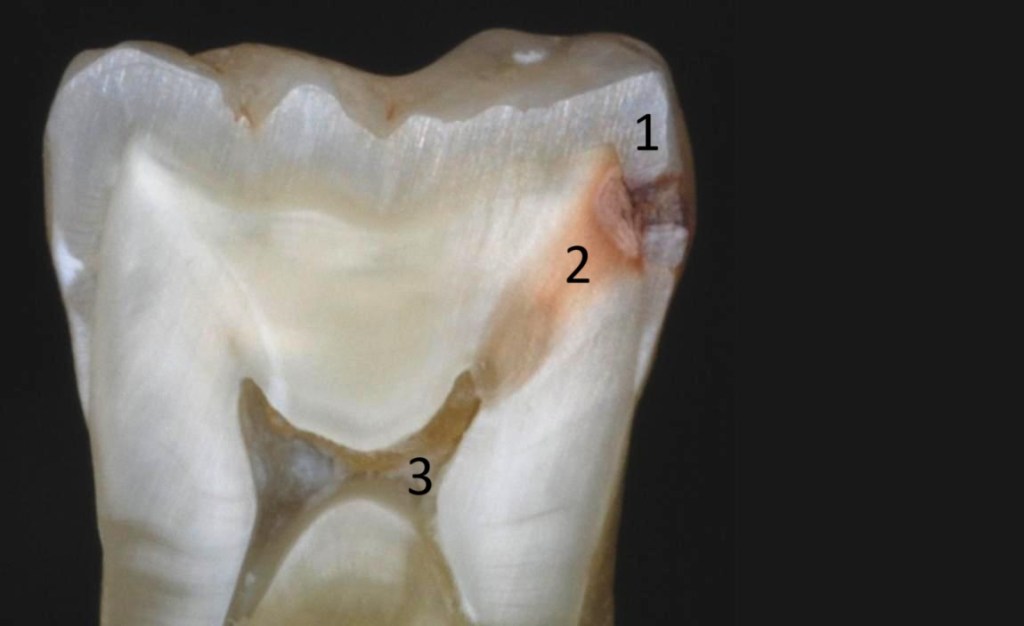

A fogzománc bizonyos mértékű ásványianyag-tartalom kioldódása után a baktériumok átjutnak a fog védőburkán (1) és a dentin destrukciójával (2) jutnak el a fog belsejében található fogideg kamrához (3). Ezen folyamat időbeli lejátszódása évekig is eltarthat, de akár hónapok alatt is bekövetkezhet.

Amennyiben a páciens időben érkezik (1, 2) és a fogkorona destrukciója még nem túl nagy kiterjedésű, akkor a legkevésbé invazív fogászati beavatkozással megállítható a további fogkárosodás, visszaépíthető a fog eredeti formájára, és újra funkcióképessé, jól tisztíthatóvá és esztétikussá válhat, további szövődményektől mentesen. Ennek elérése -legmagasabb színvonalon, legalaposabban- az akár 25x nagyításra is képes fogászati mikroszkóppal kivitelezhető.